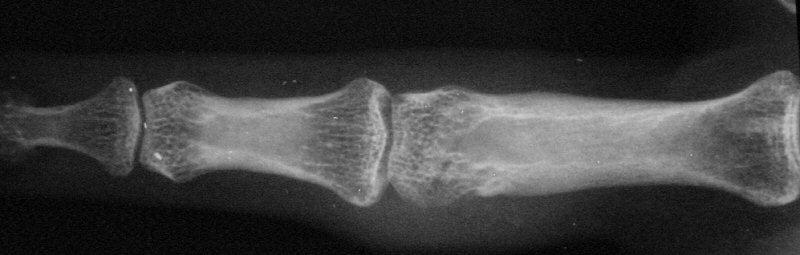

Case 1. 14 year old boy with radial prominence and ulnar deviation of the middle finger proximal interphalangeal joint. Painless, no history of trauma.

Radiographs showing well circumscribed calcification at the  proximal phalanx collateral ligament origin, 10 degrees of lateral angulation.